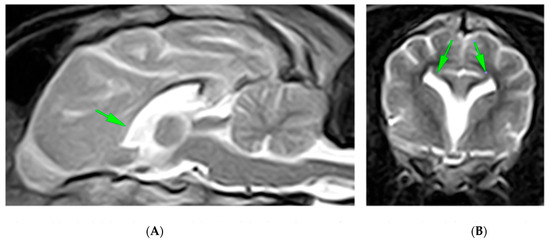

2. Case Presentation